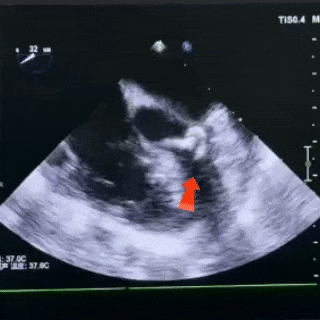

锁定前观察

双盘展开后,封堵器骑跨于室间隔

彩色血流显示无残余分流